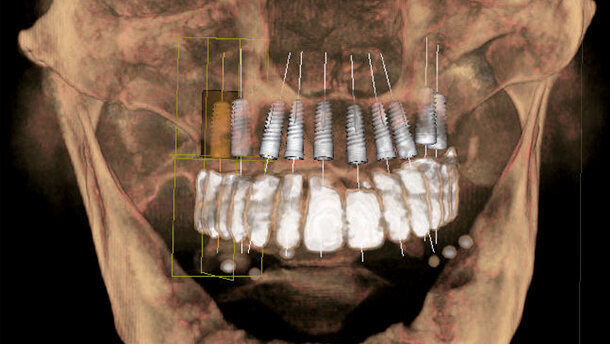

Mascellare edentulo

La pianificazione tridimensionale è di vitale importanza per la determinazione del metodo implantare nelle mascelle edentule. Ad esempio, si deve decidere se e di quale misura dev’essere l’aumento richiesto e se è consigliabile una protesi rimovibile o fissa. Per quanto riguarda l’ultimo punto, si deve anche decidere se è possibile un’ampia sostituzione di denti singoli, se si devono usare ponti piccoli o grandi, e se una maggiore distanza intermascellare deve essere riempita protesicamente con corone più lunghe o con un sostituto della mucosa. Il numero di impianti per protesi dentali fisse include il concetto All-on-4 (Nobel Biocare), le raccomandazioni della Consensus conference di sei impianti nella mandibola e otto nella mascella, e la ricostruzione dente per dente fino al primo molare. La moltitudine di informazioni sulla pianificazione e sulle possibilità di trattamento, richiede una grande progettazione, che è sempre giustificata a causa delle sue importanti conseguenze. In questo caso non è opportuna la progettazione basata su modelli digitali, poiché il supporto delle guance e delle labbra è importante per la protesi e può essere determinato solo con l’aiuto di e per ogni paziente. Qui i vantaggi della pianificazione protesica sono particolarmente evidenti. Arcate edentule richiedono spesso un approccio particolare (vedi Figg. 4a-b come esempio). È spesso necessario un ampio aumento (Figg. 5a-f). La lunghezza dei denti necessaria, tuttavia, deve essere chiarita con il paziente prima del trattamento e dipende dalla quantità di dente visualizzato con le labbra a riposo (Fig. 5e). Con molta frequenza, gli impianti vengono posizionati nelle zone interforaminali della mandibola, spesso perché l’aumento esteso è ancora problematico nella zona laterale della mandibola. Le Figure 6a e 6b mostrano un paziente con sei impianti e un ponte lungo. Anche nei casi di implantologia apparentemente semplice per protesi rimovibili in una mandibola edentula, sono necessari la programmazione e un modello in 3D per verificare la ricostruzione funzionale e il sostegno dei tessuti molli. Inoltre, essi possono essere di aiuto per decidere le posizioni degli impianti insieme all’odontotecnico e per prevedere lo spazio adeguato per il sistema di connessione.